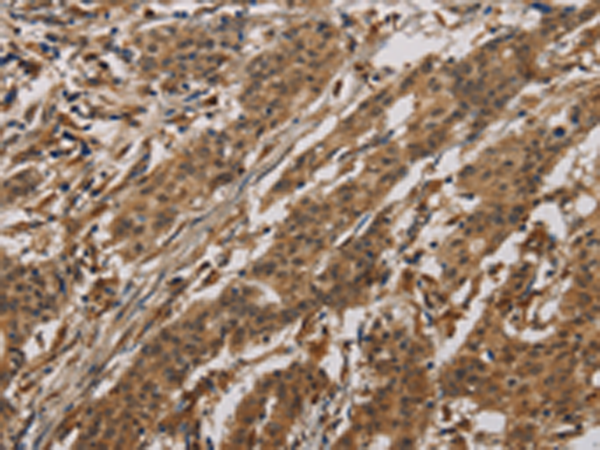

分类: 科研抗体货号: P10760别名: CKLFH; CKLFH1; CKLFSF1应用: IHC反应种属: Human